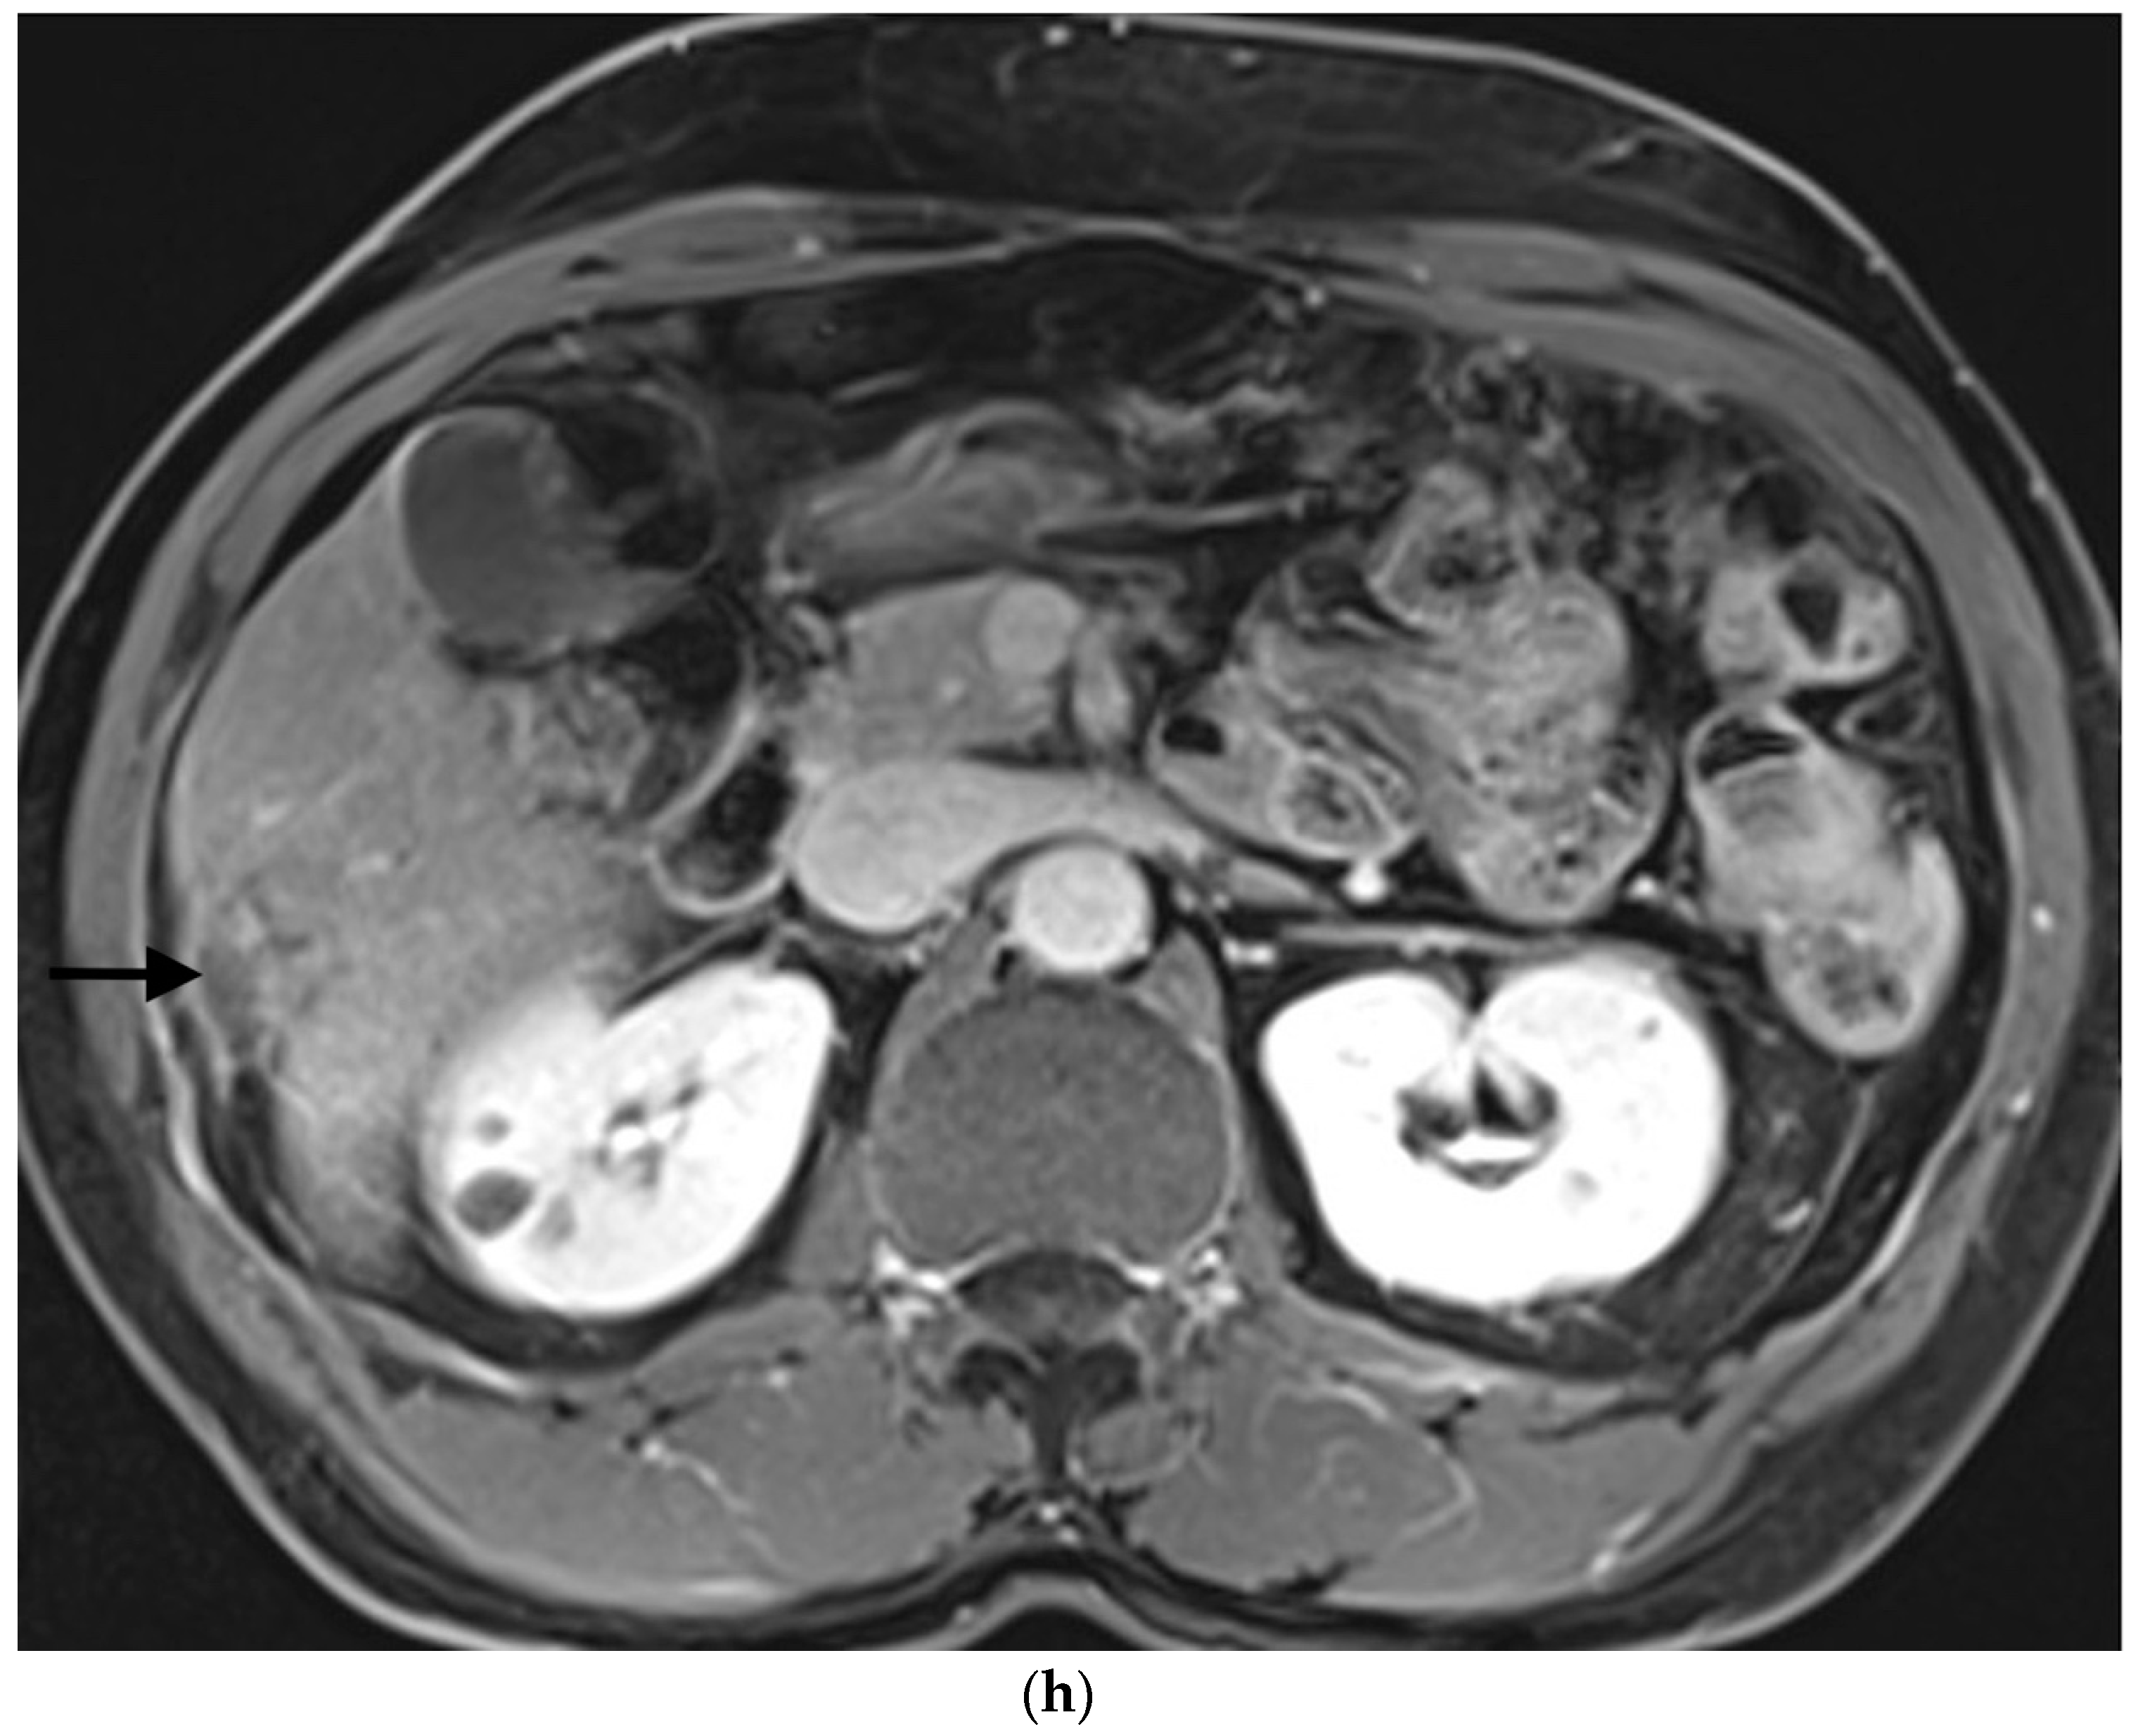

2.4. Selective Arterial Embolization Procedure